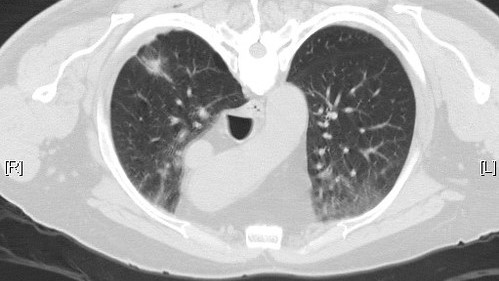

Σε ετήσια εξέταση αξονικής τομογραφίας θώρακα χαμηλής δόσης πρέπει να υποβάλλονται όλοι οι καπνιστές από τα 50 τους και μετά, έστω κι αν έχουν κόψει το τσιγάρο για μια 15ετία.

Ο προσυμπτωματικός έλεγχος του καρκίνου πνεύμονα αφορά όσους έχουν διανύσει τουλάχιστον 20 χρόνια καπνίσματος με έναή περισσότερα πακέτα τσιγάρα την ημέρα.

«Πέραν της πρωτογενούς πρόληψης που περιλαμβάνει την μη έναρξη του καπνίσματος, ποτέ, στη ζωή ενός ατόμου, η οποία διατυπώνεται συστηματικά και διαχρονικά από τους γιατρούς, η μείωση του κινδύνου για καρκίνο πνεύμονα μπορεί να επιτευχθεί και με αποφυγή έκθεσης σε ραδόνιο ή αμίαντο ή στο παθητικό κάπνισμα, με υγιεινή διατροφή και άσκηση», επεσήμανε ο κ. Κατιρτζόγλου, ενώ συνέχισε αναφερόμενος στη δευτερογενή πρόληψη που αφορά τον προσυμπτωματικό έλεγχο του καρκίνου πνεύμονα (screening), ο οποίος περιλαμβάνει την ετήσια διενέργεια χαμηλής δόσης αξονικής τομογραφίας θώρακα (LowDoseChestCT, LDCT) σε άτομα ηλικίας μεταξύ 50 και 75-80 ετών,που συνεχίζουν να καπνίζουν ή που έχουν ιστορικό καπνίσματος στη ζωή τους τουλάχιστον ίσο με 20 πακέτα-έτη ή άτομα που κάπνιζαν στο παρελθόν και έχουν σταματήσει το κάπνισμα μέσα στα τελευταία 15 έτη, άτομα δηλαδή που θεωρούνται «υψηλού κινδύνου» για καρκίνο πνεύμονα.